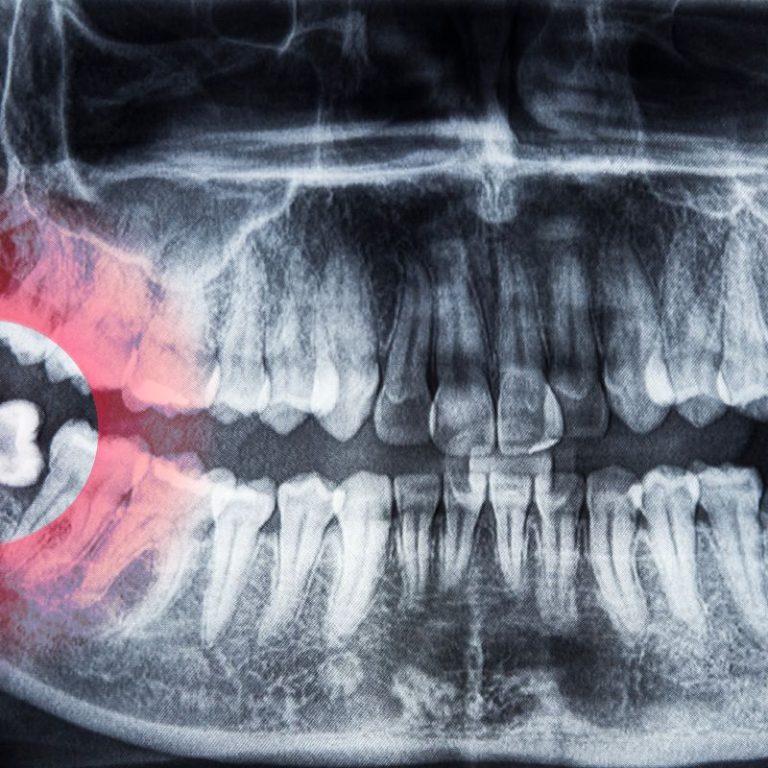

Signs You Might Need Your Wisdom Teeth Out What Are Wisdom Teeth?Wisdom teeth or third molars are the final …

Why Do Wisdom Teeth Cause So Many Problems? Almost everyone knows someone who’s had their wisdom teeth removed, …